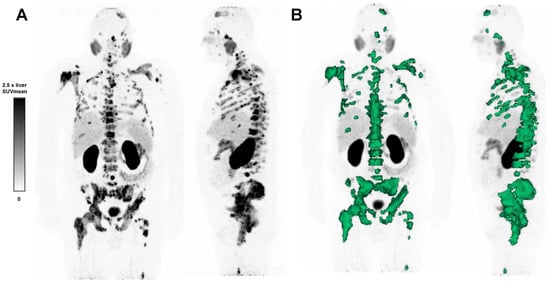

TLP, defined as the summed products of volume x uptake (as reflected by SUVmean) of all tumor lesions [28], was calculated employing a semiautomatic tumor segmentation algorithm based on that of Ferdinandus et al. [29], with a threshold of SUV ≥ 3 (Figure 1). Sites of probable 68Ga-PSMA-11 physiological uptake with an SUV above this threshold were manually excluded. Syngo.Via Enterprise VB 60 software (Siemens, Erlangen, Germany) was used.

Figure 1.

(A) 68Ga-PSMA-11 PET maximum intensity projection image of a patient with advanced mCRPC, and (B) semi-automatic tumor segmentation in that patient using Syngo.via Enterprise VB 60 (Siemens, Erlangen, Germany). The PSMA-positive tumor volume is delineated in green. The SUVmean window was set at 0–2.5 times the SUVmean of the healthy liver.